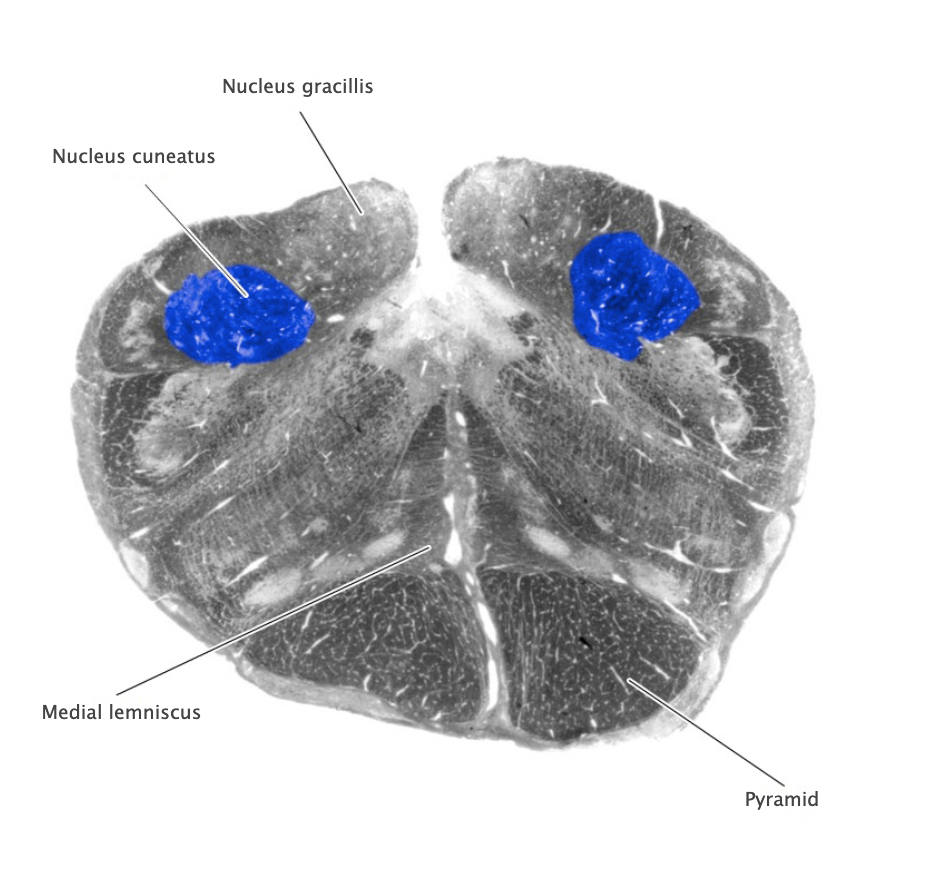

Dorsal column nuclei

Gracile nucleus and cuneate nucleus; contain the second-order sensory neurons that relay mechanosensory information from peripheral receptors in the body (excluding the face) to the thalamus via the medial lemniscus. The dorsal column nuclei are located in the lower medulla.

Nucleus cuneatus

Dorsal column nucleus in the lower medulla; contains second-order sensory neurons that relay mechanosensory information from peripheral receptors in the upper extremities to the thalamus via the medial lemniscus.

Nucleus gracilis

Nucleus containing the second-order sensory neurons that relay mechanosensory information from peripheral receptors in the lower body to the thalamus via the medial lemniscus, located in the lower medulla (also called the "gracile nucleus"). The nucleus gracilis also relays visceral pain information from second-order neurons in the central spinal cord to the thalamus.